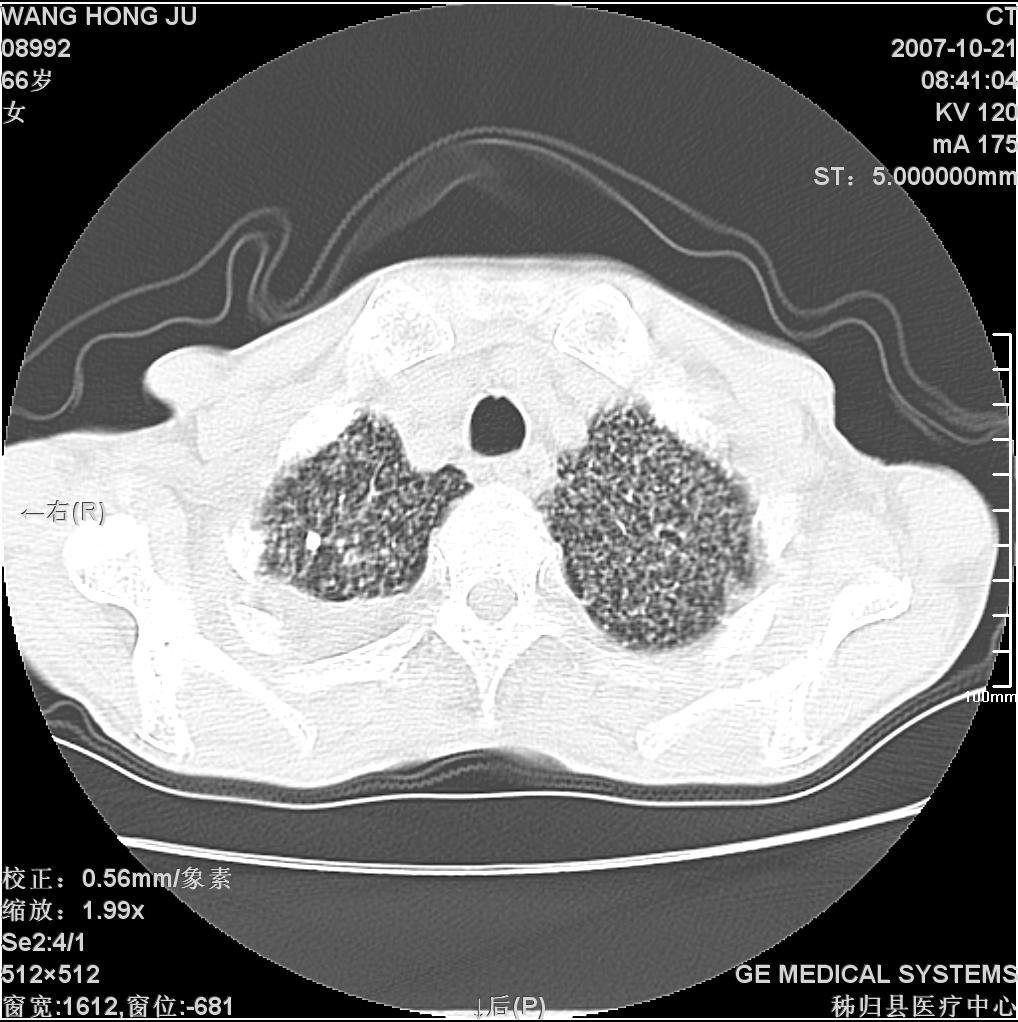

患者咳嗽月余,高热数天,咳黄色稍脓痰。

双肺野分布多个小结节状高密度影,其内散在斑片状模糊影,气管。支气管通畅,纵隔内淋巴结钙化,胸膜局限性增厚粘连,胸腔少量积液。结合病史考虑结核并感染的可能性大,胸膜炎并积液。肺泡癌待排。

纵隔内见钙化的淋巴节,上肺见钙化灶,双肺均匀弥漫分布小结节影,边缘较清楚,能不能考虑是在矽肺的基础上并发的结核和感染,请详细了解病史结合临床.